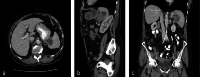

Figure 1

Figure 1. Axial (a), sagittal (b), and coronal (c) planes of CT showing a complex mass with a cystic component arising from the splenic hilum.